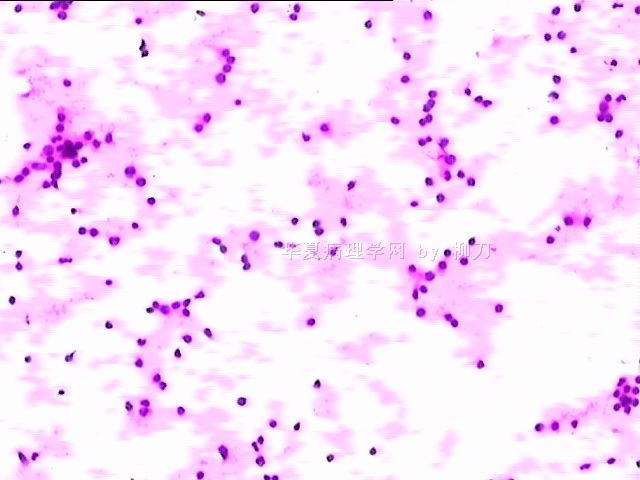

78y,男,胸水。 大家看看那些小于淋巴细胞的东东。

孢子?

图6感觉象是污染的孢子之类的东西。好好回忆一下,制片过程?容器?有没有污染的 可能?

但,最后一图的组织细胞内吞噬现象,怎么解释。

离体的细胞在一定的时间内还是活细胞,所以我推测吞噬细胞可能还是有一定的吞噬功能的。不过,确实也不能就排除了在活体内的微生物感染的可能。结合临床应该能够得到一定程度的澄清。

像是孢子

同意孢子